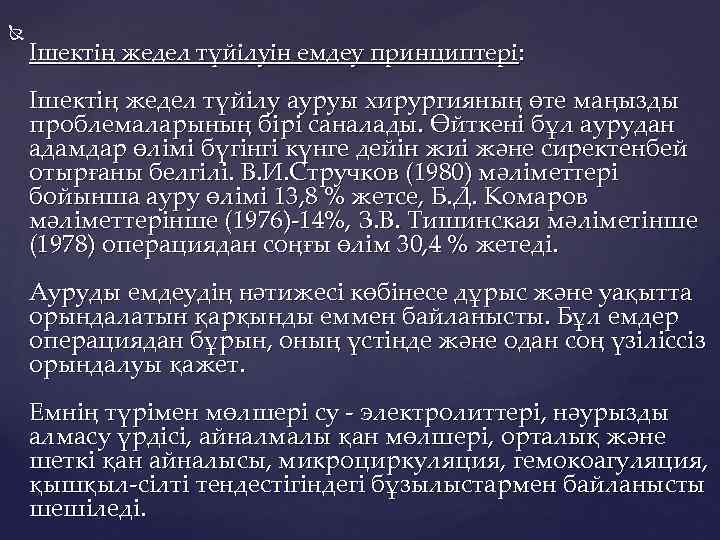

Ішектің жедел түйілуін емдеу принциптері: Ішектің жедел түйілу ауруы хирургияның өте маңызды проблемаларының бірі саналады. Өйткені бұл аурудан адамдар өлімі бүгінгі күнге дейін жиі және сиректенбей отырғаны белгілі. В. И. Стручков (1980) мәліметтері бойынша ауру өлімі 13, 8 % жетсе, Б. Д. Комаров мәліметтерінше (1976)-14%, З. В. Тишинская мәліметінше (1978) операциядан соңғы өлім 30, 4 % жетеді. Ауруды емдеудің нәтижесі көбінесе дұрыс және уақытта орындалатын қарқынды еммен байланысты. Бұл емдер операциядан бұрын, оның үстінде және одан соң үзіліссіз орындалуы қажет. Емнің түрімен мөлшері су - электролиттері, нәурызды алмасу үрдісі, айналмалы қан мөлшері, орталық және шеткі қан айналысы, микроциркуляция, гемокоагуляция, қышқыл-сілті тендестігіндегі бұзылыстармен байланысты шешіледі.